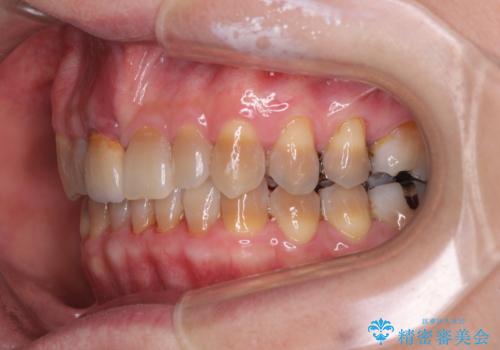

- 前歯のデコボコと、顎に負担のかかる歯並びを改善したいとのことで来院された患者様です。

うまく歯ぎしりができず、強く食いしばりをしてしまう咬み合わせであったため、奥歯に非常に負担がかかっていました。

インビザラインを用いて前歯のデコボコを改善するとともに、奥歯の咬み合わせを変えてスムーズに歯ぎしりできるように排列していくこととしました。